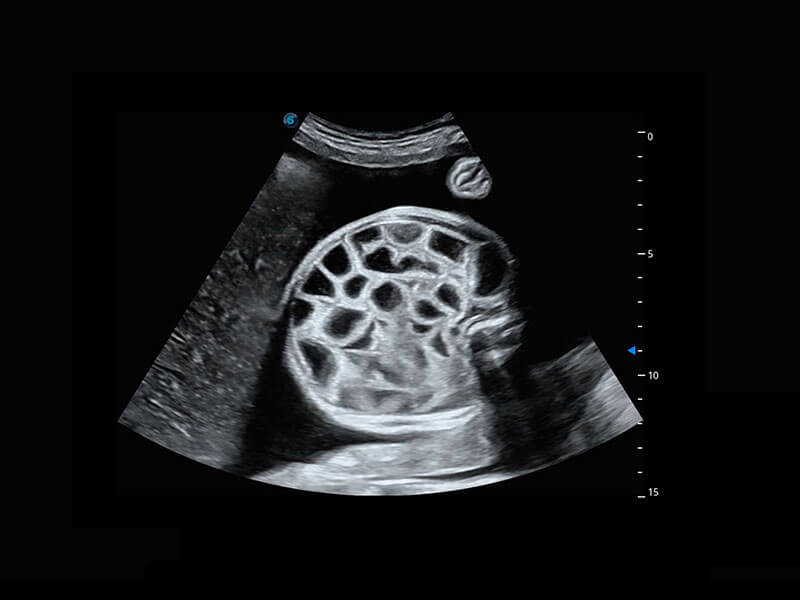

P60提供簡(jiǎn)單易學(xué)易用的高端診斷工具,為您中晚孕篩查提供快速清晰的解剖信息。

1 OFD(HC): 87.03 mm

HC: 251.00 mm

GA: 27w 1d

HC/AC: 96.13 %

2 BPD: 70.56 mm

GA: 28 w 2d

S-Fetus(acq.)

&

S-Fetus(meas.)

S-Fetus能夠助您在實(shí)時(shí)掃查過(guò)程中自動(dòng)識(shí)別標(biāo)準(zhǔn)切面、自動(dòng)測(cè)量并錄入報(bào)告。一個(gè)按鍵,即可快速、高效地獲取胎兒生理指標(biāo),簡(jiǎn)化您的產(chǎn)科檢查操作。